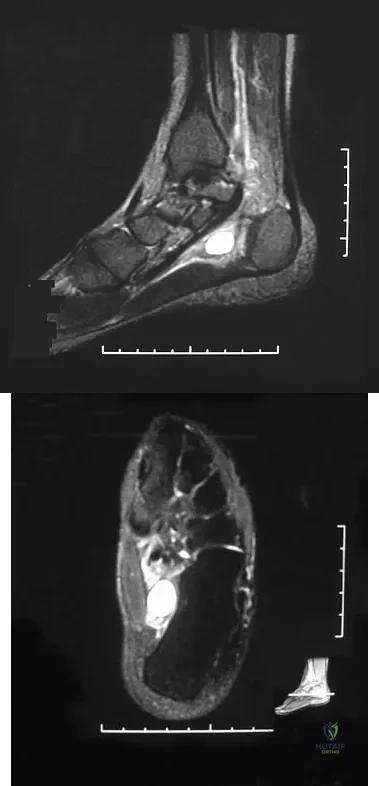

Question 75

A 37-year-old woman has had intermittent paresthesias and numbness in the plantar foot for the past 6 months. She reports that the symptoms are worse with activity, and the paresthesias are beginning to awaken her at night. MRI scans are shown in Figures 6a and 6b. What is the most likely diagnosis?

Explanation